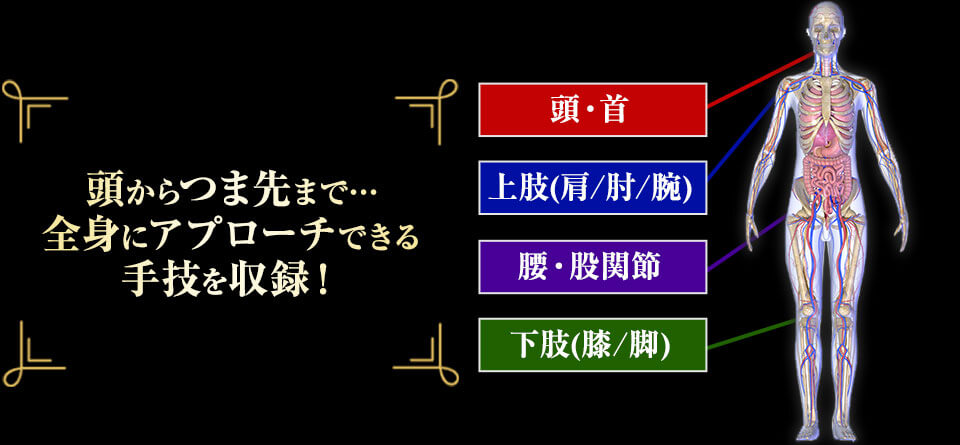

あらゆる症状に対応できる【万能性】

| 頭・首 | 首の寝違え 顎関節症 頭痛 眼精疲労 頸椎椎間板ヘルニア 首こり 緑内障…etc. |

|---|---|

| 肩・肘・腕 | 肩腱板断裂 肩こり 痺れ 五十肩 腱鞘炎 胸郭出口症候群 関節リウマチ 手根管症候群 野球肩 野球肘…etc. |

| 腰・股関節 | 脊柱管狭窄症 腰痛 腰椎分離症 ギックリ腰 すべり症 骨粗鬆症 椎間板ヘルニア 尾骨痛 変形性股関節症 変形性脊椎症 股関節痛…etc. |

| 膝・脚 | しびれ 変形性膝関節症 膝関節痛 オスグッド シンスプリント 腸脛靭帯炎 アキレス腱炎 腓骨筋腱炎 足底筋膜炎 セーバー病…etc. |

| 自律神経 その他 |

脳梗塞片麻痺 脳出血片麻痺 パーキンソン病 不眠 パニック障害 食欲不振 逆流性食道炎 脳性麻痺 脊髄小脳変性症 喘息 冷え性 倦怠感 むくみ うつ 不安(浅い呼吸)…etc. |

| 頭・首 | 首痛、ムチウチ、寝違え、頭痛、 ストレートネック、頚椎症、 頸椎椎間板ヘルニア、首コリ、 緑内障、頭痛、耳鳴り、 むくみ、だるさ |

|---|---|

| 肩・肘・腕 | 肩腱板断裂、肩こり、五十肩、 しびれ、腱鞘炎、関節リウマチ、 ばね指、 テニス肘、手根管症候群、 野球肩、野球肘、胸郭出口症候群 |

| 腰・股関節 | 脊柱管狭窄症、腰痛、腰椎分離症、 すべり症、ギックリ腰、 椎間板ヘルニア、骨粗鬆症、 尾骨痛、変形性股関節症、 股関節痛、変形性脊椎症 |

| 膝、脚 | 変形性膝関節症、 O脚、オスグッド、 シンスプリント、腸腰靭帯炎、 アキレス腱炎、セーバー病、 足底腱膜炎、腓骨筋腱炎 |

| 自律神経 | パニック障害、食欲不振、 逆流性食道炎、うつ、冷え性、 喘息、不妊症、不眠、立ち眩み、 慢性疲労、眼精疲労 |

| 難治症 | 脳梗塞片麻痺、パーキンソン病、 脳出血片麻痺、 脊髄小脳変性症、脳性麻痺、 頸神経叢麻痺…etc |

※治療院にくる患者さんの ほぼ全ての症状に対応可能です